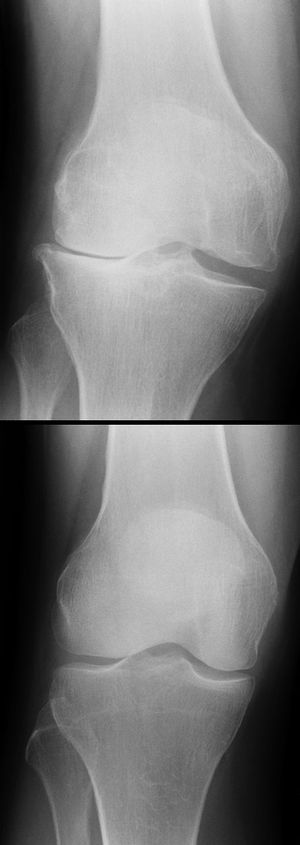

Röntgenbild einer lateralen Gonarthrose (oben) im Vergleich zu einem normalen Kniegelenk (unten)